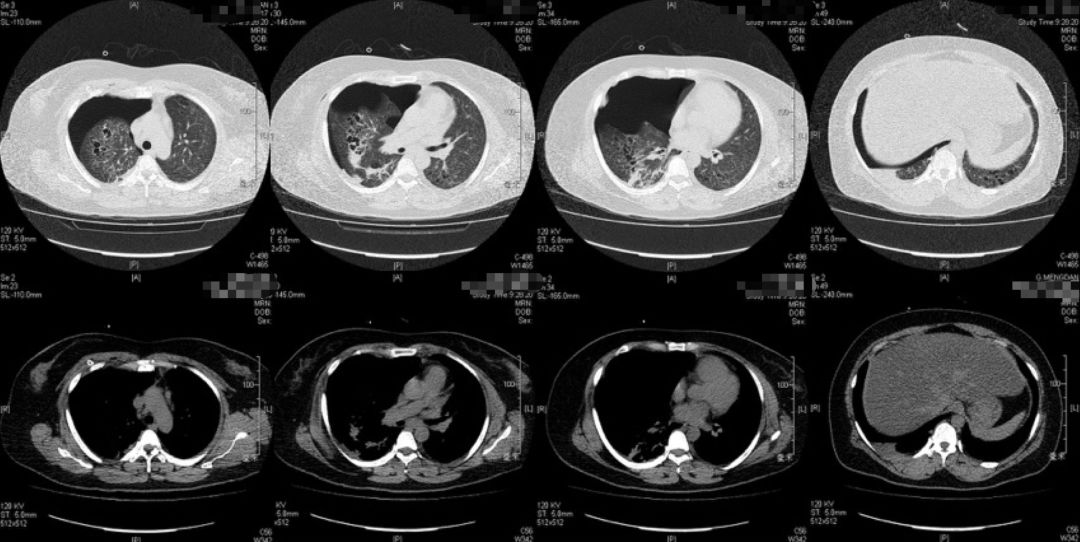

2019-05-31胸部CT:

1、治疗后患者体温平,复查CT提示气胸吸收,2019-05-26拔除胸腔闭式引流管,2019-06-06出院;

放射科张兴伟副主任医师

本例患者的胸部CT主要表现为两肺相对弥漫分布的怪异的气囊和结节,气囊为薄壁,以中上肺分布为主,沿支气管血管束分布,符合LCH细胞沿支气管分布的特点,并且有可能会引起支气管阻塞,类似活瓣样的作用,因此囊腔的形状怪异。胸腔镜术后的CT表现,可能是局部阻塞牵拉引起疱的加重,也可能是胸膜粘连后局限性的气胸的表现。